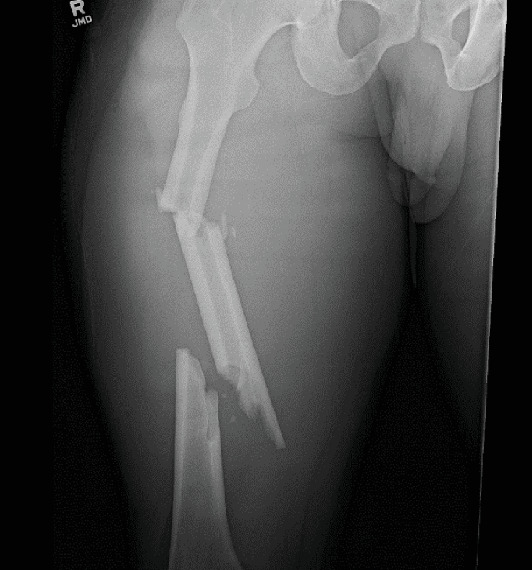

This case report from a Level 1 trauma center describes a novel surgical technique to remove a cannulated intramedullary nail, broken at the distal aspect, from the femur. We present a 40-year-old male who sustained a hardware failure, breaking his medullary nail at the distal aspect 7 weeks postoperatively while performing water aerobics. The broken implant was successfully extracted without complication, and a subsequent nail was exchanged. A benefit of this technique is avoiding a femoral osteotomy, which may prove useful for the unique and difficult case of distally broken nails.